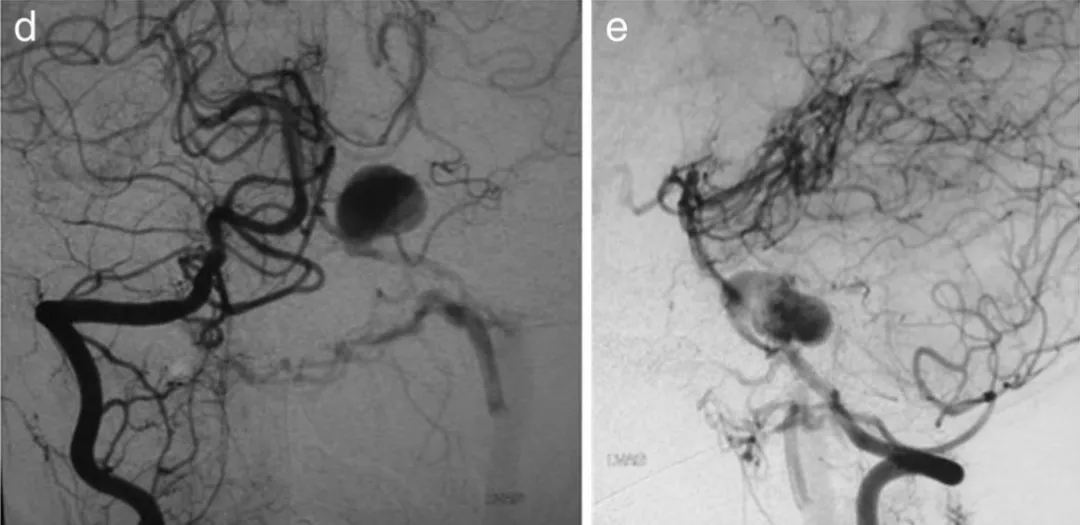

更棘手的是,入院第7天的血管造影证实,这个动脉瘤不仅是创伤后形成的,还合并了动静脉瘘——一条异常静脉直接从动脉瘤瘤顶引流至颈内静脉,相当于血管系统出现了“短路”。

图a,b,c为第7天的右椎动脉造影。动脉瘤位于左AICA的近端。

更危险的是,14天后复查造影,动脉瘤已经明显增大,随时可能破裂大出血。

图d,e为第14天右椎动脉造影。动脉瘤扩大,房室瘘更加明显。